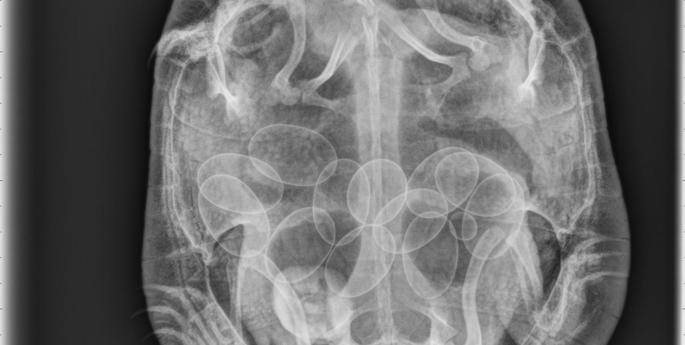

A happy ending for eastern long-necked turtleA happy ending for eastern long-necked turtle

A happy ending for eastern long-necked turtle

Vet staff got a bit more than expected when this turtle recovered at Taronga Western Plains Zoo Wild Life Hospital.